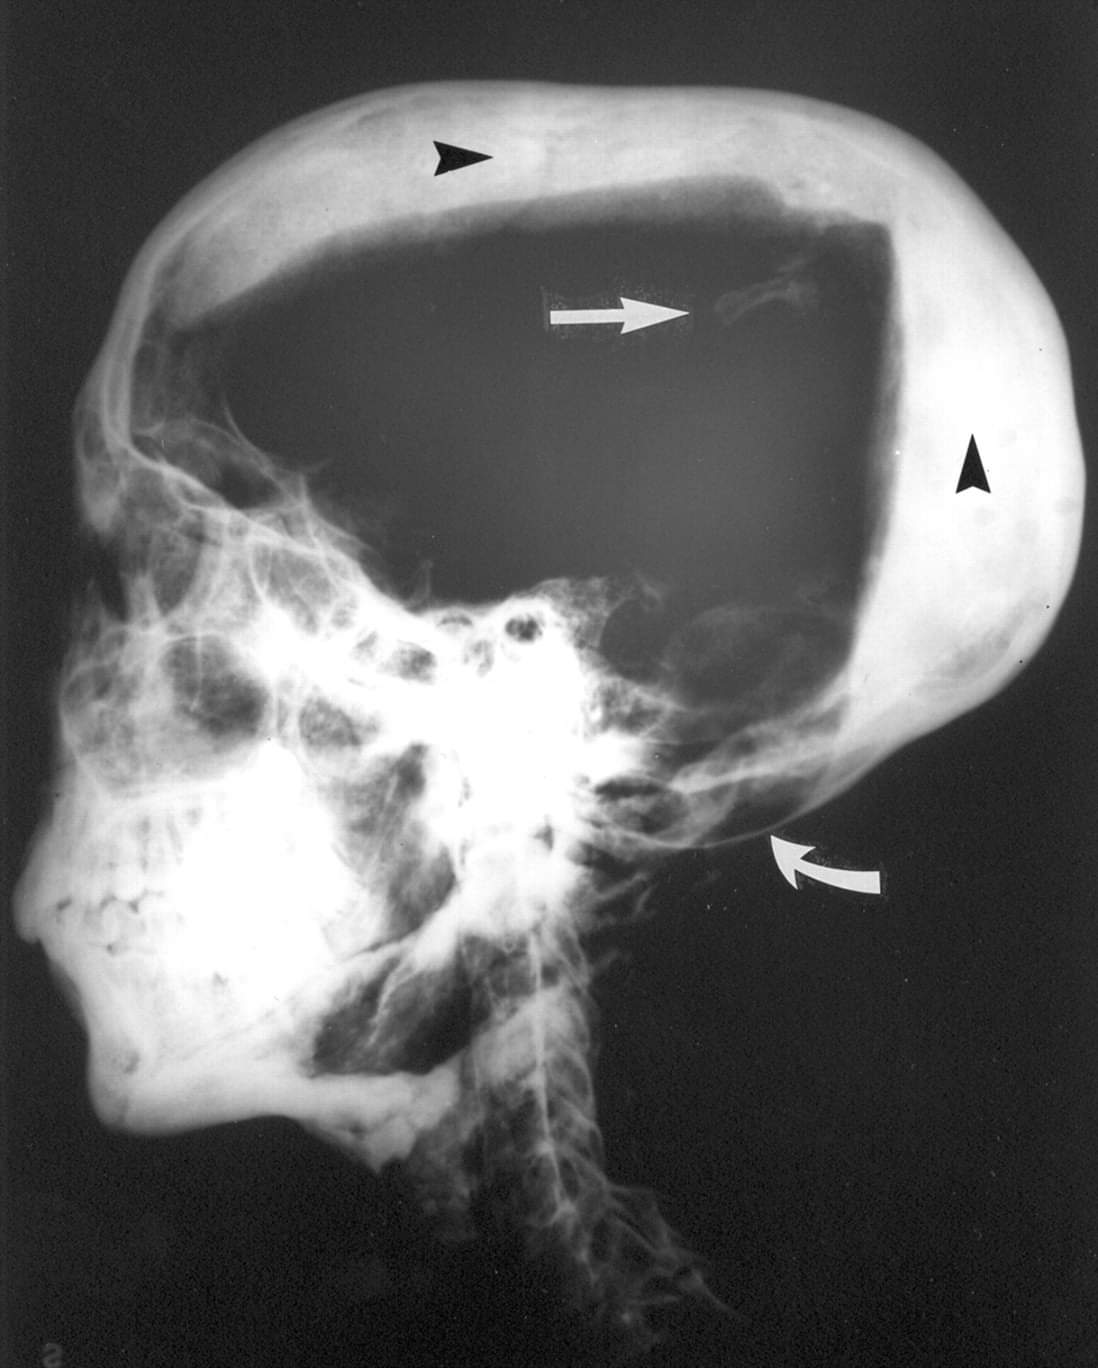

1968년 리버풀 대학교(University of Liverpool) 해부학 교수인 로널드 G. 해리슨(Ronald G. Harrison: 1921-1983년) 박사가 마침내 투탕카멘 미라에 대한 엑스레이 검진을 수행했습니다(아래 그림 참조).

이 과정에서 해리슨 박사는 왕이 미라로 처리되기 전에 갈비뼈가 부러졌고 두개골 내부에 뼛조각이 있다는 사실을 발견했습니다.

또한 해리슨 박사가 촬영한 엑스레이 사진에는 머리와 목이 만나는 두개골 하단에 흐릿한 부분이 발견되었는데 이에 대해 그는 이 흐릿한 부분의 엑스레이 농도가 정상치를 벗어나지는 않았으나 이 부분이 뇌막조직 하부에 출혈이 있었다는 것을 의미할 수도 있으며 따라서 왕의 후두부가 가격 당했을 가능성(살해 가능성에 대해서는 언급하지 않았습니다)이 있다는 견해를 조심스럽게 제시했습니다.